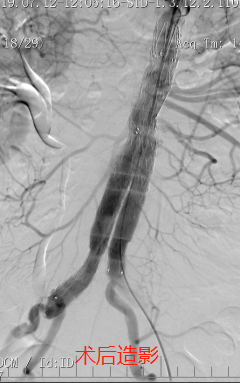

手术方式包括两类:一是“巨创”,就是传统的开刀手术方法,但这种手术创伤巨大,大部分患者术后需要进入重症监护病房过渡。如果病人一般的情况比较好,对手术的耐受度比较高,采取这种方法是一个很好的治疗手段。二是“微创”,还有一种方法就是近年来发展迅速的微创技术-腹主动脉瘤腔内修复术(Endovascular Aortic aneurysm Repair, EVAR),就是把一个带膜的大支架放在主动脉里边,使得血液通过这个支架内流动,这种治疗方式不但具有和开腹手术一样的效果,而且创伤小、恢复快。目前我院血管甲状腺外科已经常规开展以上两项技术。

随着技术和材料的进步,我院血管甲状腺外科在“微创”的基础上,逐渐推广了“无创”的腹主动脉瘤腔内隔绝术,也就是经皮股动脉穿刺入路的腹主动脉瘤腔内修复术(Percutaneous Endovascular Aortic aneurysmRepair, PEVAR),没有切口,只有两个小小的穿刺点,其创伤更小,病人恢复更快。同时,还对解剖条件合适但合并症较多的患者,成功实行了局麻下P-EVAR术,最大程度降低了麻醉风险。目前我院血管甲状腺外科已成功完成近10例腹主动脉瘤的穿刺微创腔内修复手术,无一例并发症,患者术后恢复很快,手术当日就能恢复饮食,术后第一日就可以下床活动,很快就可以康复出院,以最小的创伤方式解决了最危险的主动脉疾病,该技术达到省内领先,国内先进水平。